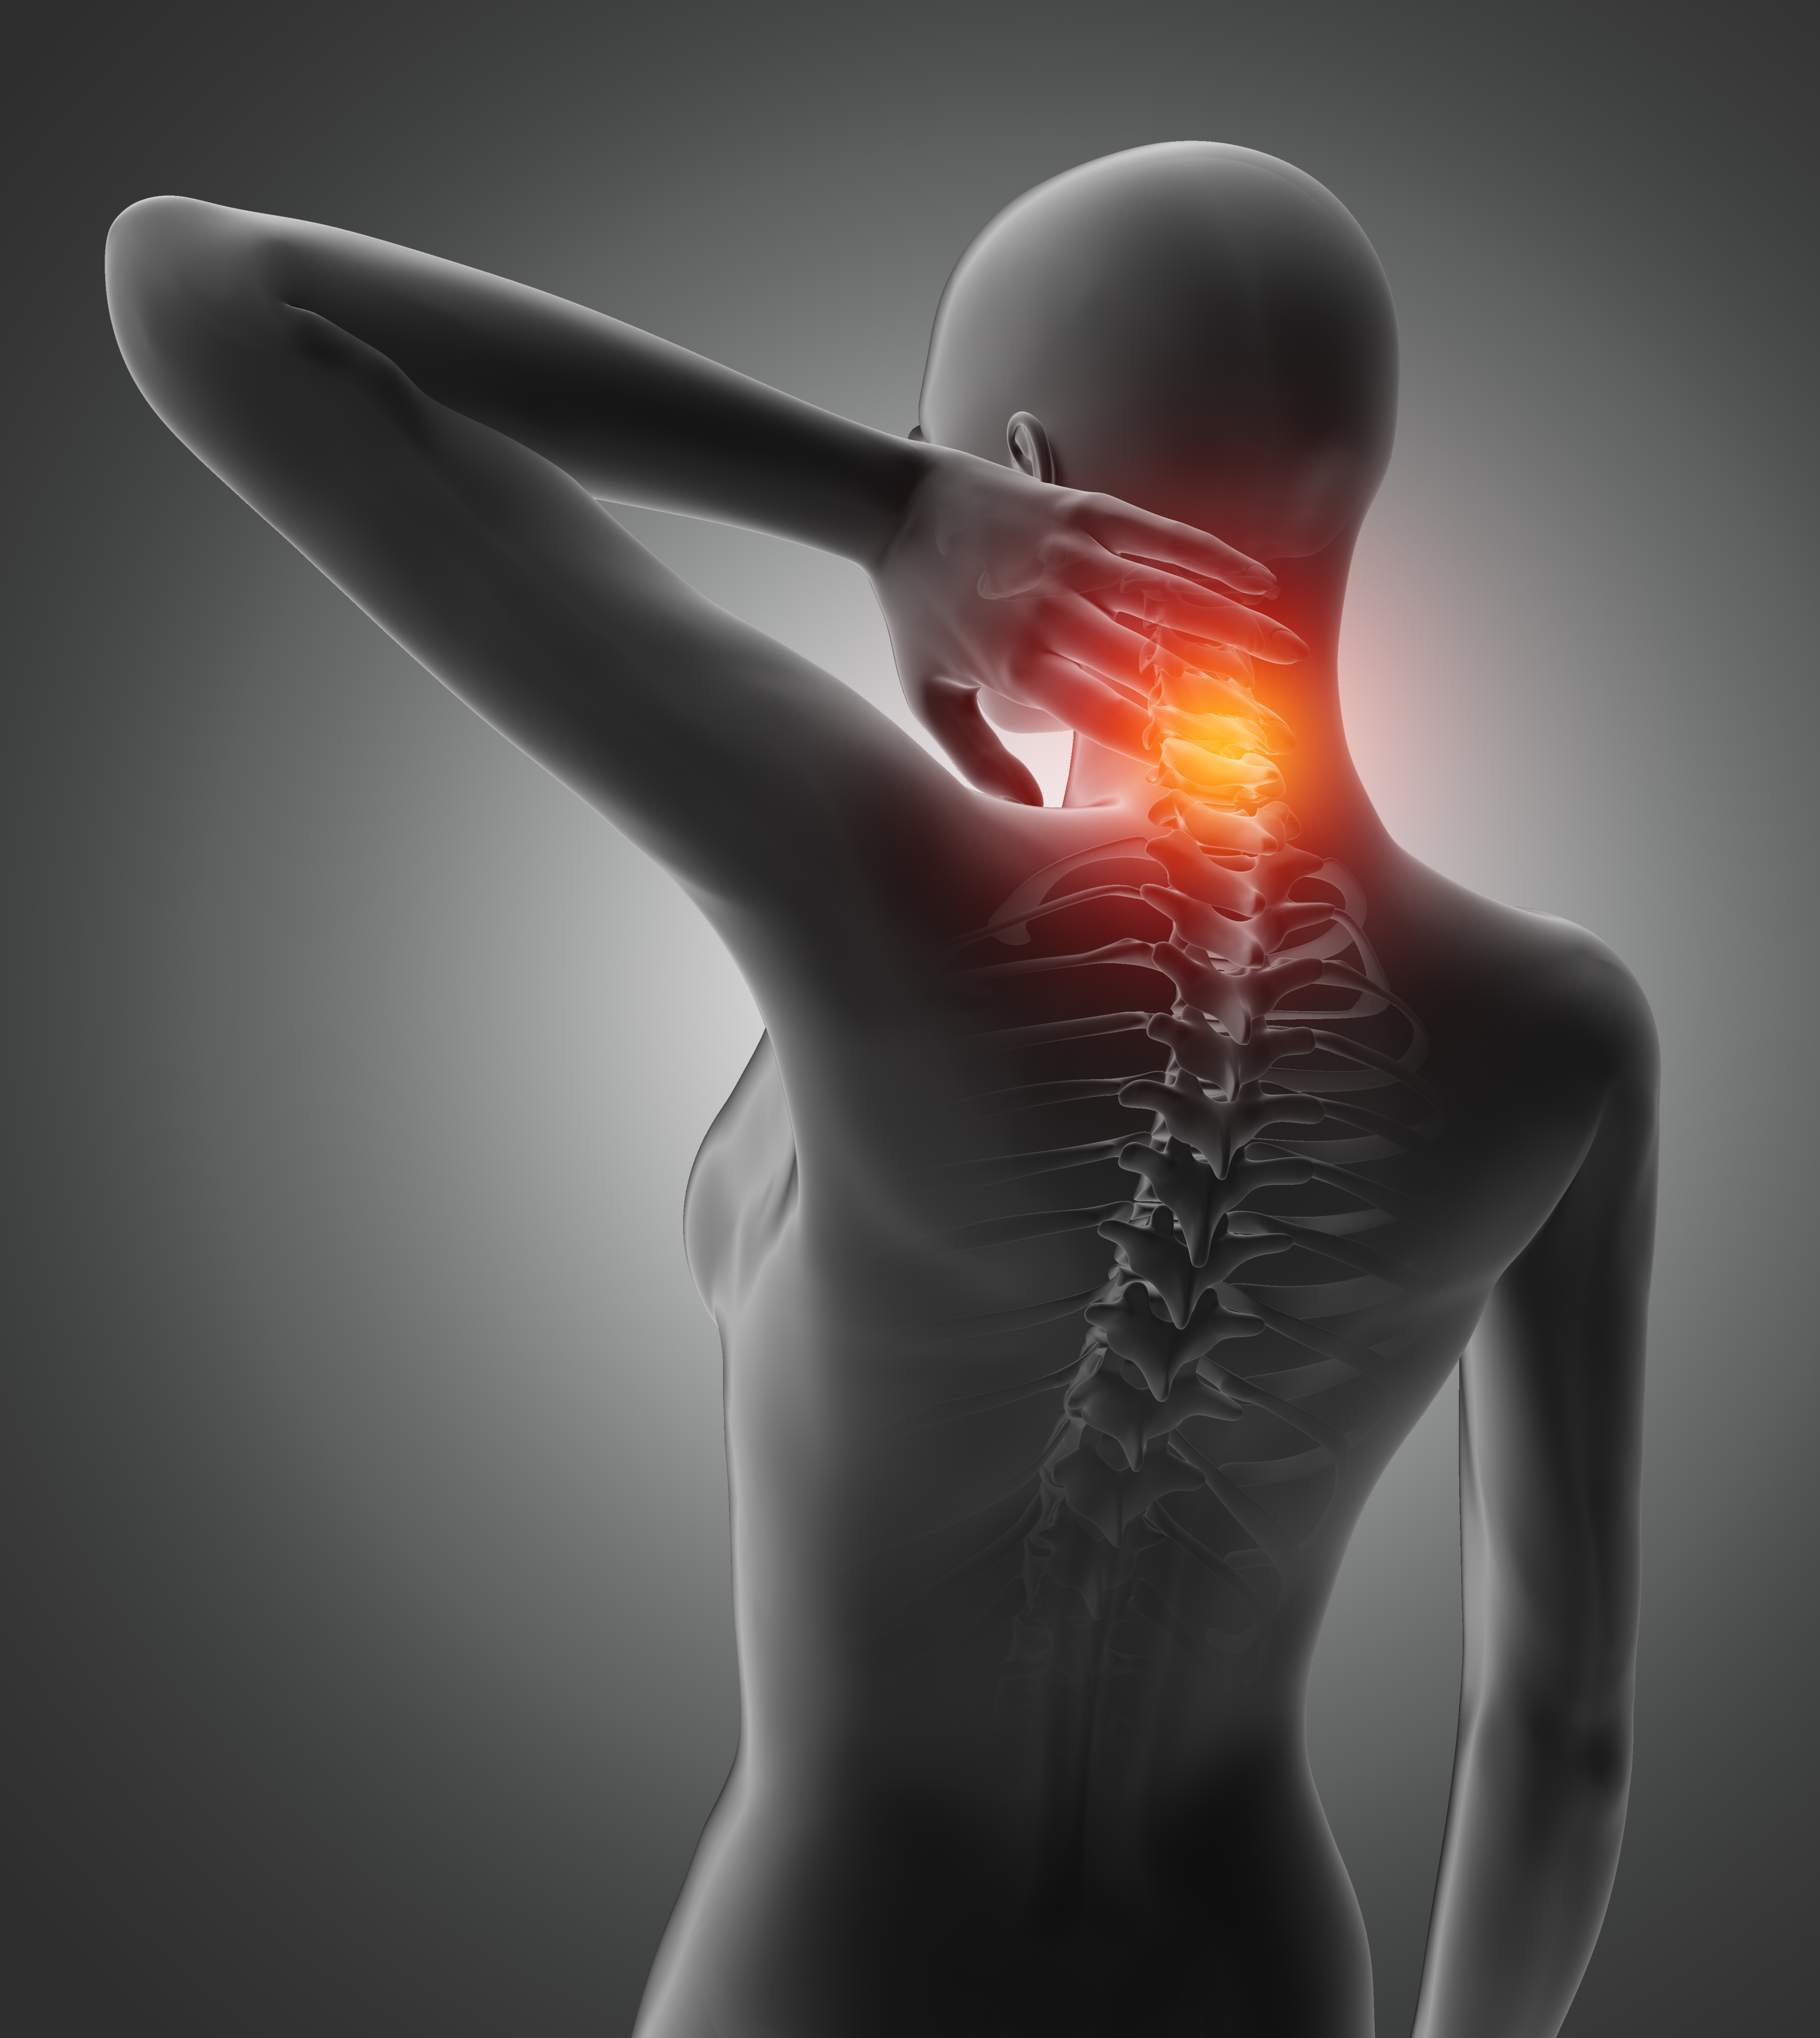

Sabe aquela “corcundinha” logo atrás do pescoço, o desconforto nas costas, tensão nos ombros, barriga saliente e dor de cabeça que pensamos ser decorrente da “idade“? Podem ser sinais e sintomas de constante postura incorreta.

A coluna apresenta curvaturas naturais, a curva atrás do pescoço (lordose cervical), na parte superior das costas (cifose torácica) e na inferior das costas (lordose lombar). Quando essas curvaturas ficam acentuadas dizemos hiperlordose e hipercifose. A escoliose é um desvio que torna a coluna em “S“, sendo um quadro mais crítico para o tratamento e, dependendo da idade da pessoa, apenas cirurgia para a sua correção.

O aumento da cifose torácica é mais comum em idosos devido à osteoporose e à perda muscular que leva ao enfraquecimento deixando a pessoa com aquele perfil estereotipado de “velhinha curvada da bengala“. O problema é que as pessoas estão adquirindo esse aspecto bem mais jovens. Inclusive, nas minhas pesquisas, encontrei muitas matérias direcionadas aos adolescentes.

Na verdade, isso acontece pela postura que todo mundo vem adotando para usar os smarthphones (projetando a cabeça para frente e para baixo), que além da corcunda, aumenta a lordose cervical. Tudo isso combinado ao sedentarismo aumenta o acumulo de gordura na região formando aquela corcova logo abaixo do pescoço.

Essa postura incorreta traz dor, reduz a amplitude de movimentos, prejudica a respiração e compromete a qualidade de vida. E vamos ser sinceras, não é nada bonito ostentar um perfil curvado assim, certo?